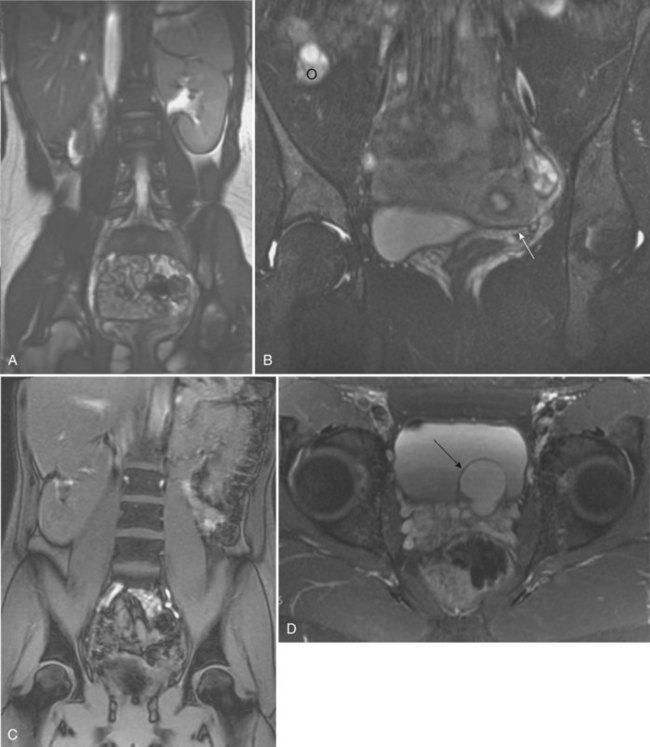

The ipsilateral ureter is completely absent in about 60% of the cases (Fortune, 1927; Collins, 1932; Ashley and Mostofi, 1960). In the Ashley and Mostofi series, 19 of 232 with URA had only a portion of the lower end of the ureter present. There were no normally developed ureters reaching the level of the normal kidney. In most cases of complete absence of the ureters, the bladder showed no evidence of a ureteric orifice with failure of ipsilateral trigone development (Ashley and Mostofi, 1960). Cell lineage studies using a murine model show that the trigone has a urogenital sinus origin and should form normally (Viana et al, 2007; Mendelsohn, 2009). The trigone may not be distinguishable from the surrounding detrusor when the intramural ureter is absent. Therefore the endoscopic appearance of the trigone in this setting has lead to the probable misnomer in the case of the “hemitrigone” (in association with complete ureteral agenesis) or “asymmetrical trigone” (in the presence of a partially developed ureter). Segmental ureteral atresia on one side has been associated with contralateral ureteral or renal ectopia (Limkakeng and Retik, 1972). Except for ectopia or malrotation, anomalies of the contralateral kidney are infrequent (Longo and Thompson, 1952; Chow et al, 2005) (Fig. 117–5). However, abnormalities of the contralateral ureter are not uncommon, including ureteropelvic and ureterovesical junction obstruction in 11% and 7%, respectively (Cascio et al, 1999), and reflux in 30% (Atiyeh et al, 1993; Cascio et al, 1999). Other urologic abnormalities are found in 65% with URA (Kaneyama et al, 2004).

Figure 117–5 Magnetic resonance imaging (MRI) showing (A) coronal scout image of right renal agenesis with the bowel occupying the right renal fossa. B, Coronal T2 fat-saturated images show left unicornuate uterus (arrow), absent right cornua, and superior location of right ovary (o). C, Coronal scout image demonstrates left renal agenesis with bowel occupying the left renal fossa and right renal malrotation. D, Transverse T2 fat-saturated image of male pelvis shows left seminal vesicle cyst (arrow).

The testis and head of the epididymis, which contain the efferent ductules derived from the mesonephric tubules, are invariably present; all structures proximal to that point, which develop from the WD (the body and tail of the epididymis, vas deferens, seminal vesicle, ampulla, and ejaculatory duct), are absent in almost 50% (Radasch, 1908; Collins, 1932; Charny and Gillenwater, 1965; Ochsner et al, 1972). Donohue and Fauver (1989) reported 79% of adult males with an absence of the vas deferens have an absent ipsilateral kidney; left-sided lesions predominated with a ratio of 3.5 : 1. However, bilateral absence of the vas has been noted with URA (McCallum et al, 2001). Occasionally, the WD structures are rudimentary or ectopic rather than absent (Holt and Peterson, 1974). Ipsilateral cryptorchidism rarely occurs. In 1914, Zinner reported a seminal vesicle cyst in association with ipsilateral renal agenesis (Pereira et al, 2009). Seminal vesicle cysts secondary to obstruction of the ejaculatory duct are currently diagnosed with increasing frequency as pelvic ultrasound examinations are performed more often (Lopez-Garcia et al, 1998; Kaneyama et al, 2004). Six cases (5%) were noted among 119 boys who were found to have URA during ultrasound screening of schoolchildren (Shieh et al, 1990). A pelvic ultrasonogram or magnetic resonance imaging (MRI) in boys diagnosed with URA may demonstrate a seminal vesicle cyst (Van den Ouden et al, 1998, Seo et al, 2009) (see Fig. 117–5). In cases of seminal vesicle cysts and URA, the ureter may insert into the prostatic urethra or seminal vesicle. Cystic dysplasia of the rete testis, a rare benign condition, is often associated with ispsilateral renal anomalies, most commonly URA (Wojcik et al, 1997; Camassei et al, 2002).

A variety of anomalies may result in the female from incomplete MD formation because of alterations in normal WD development. Approximately one fourth to one third of women with URA have an abnormality relating to WD development (Thompson and Lynn, 1966; Heinonen, 2004). Conversely, 43% of women with genital anomalies have URA (Semmens, 1962; Heinonen, 1997). The most common MD anomalies are a true unicornuate uterus with complete absence of the ipsilateral horn and fallopian tube or a bicornuate uterus with rudimentary development of the horn on the affected side (Candiani et al, 1997) (see Fig. 117–5). The fimbriated end of the fallopian tube, however, is usually fully formed and is analogous to the head of the epididymis in the male (Shumacker, 1938). Partial or complete midline fusion of the MD may result in a double (didelphys) or septate uterus with either a single or a duplicated cervix (Radasch, 1908; Fortune, 1927). Complete duplication or separation of the vagina, proximal vaginal atresia associated with a small introital dimple, and complete absence of the vagina have been reported (Woolf and Allen, 1953; D’Alberton et al, 1981). Obstruction of one side of a duplicated system is not uncommon, and unilateral hematocolpos or hydrocolpos associated with a pelvic mass and/or pain has been described in pubertal girls (Weiss and Dykhuizen, 1967; Vinstein and Franken, 1972; Gilliland and Dick, 1976; Wiersma et al, 1976; Yoder and Pfister, 1976). Smith and Laufer (2007) suggested the acronym OHVIRA to classify the syndrome of Obstructed Hemivagina and Ipsilateral Renal Anomaly. In rare instances, this anomalous condition has been mistaken for a large or infected Gartner duct cyst. Sometimes a true Gartner duct cyst has been found in a prepubertal girl in association with an ectopic ureter that is blind ending at its proximal end or one that is connected to a rudimentary kidney (Currarino, 1982). Six percent of girls with URA were found to have a Gartner cyst on mass screening of schoolchildren (Shieh et al, 1990). Infertility occurs in as many as 33% of affected women with renal agenesis and unicornuate uterus (Heinonen, 1997). When specific anomalies of the uterus, including congenital absence of the uterus, unicornuate uterus, and didelphic uterus, are found on ultrasonography or MRI, radiologic investigation of the urinary tract often demonstrates URA or other renal anomalies (Bryan et al, 1949; Phelan et al, 1953; Thompson and Lynn, 1966; Candiani et al, 1997; Heinonen, 1997, Govindarajan et al, 2008; Reichman and Laufer, 2010).